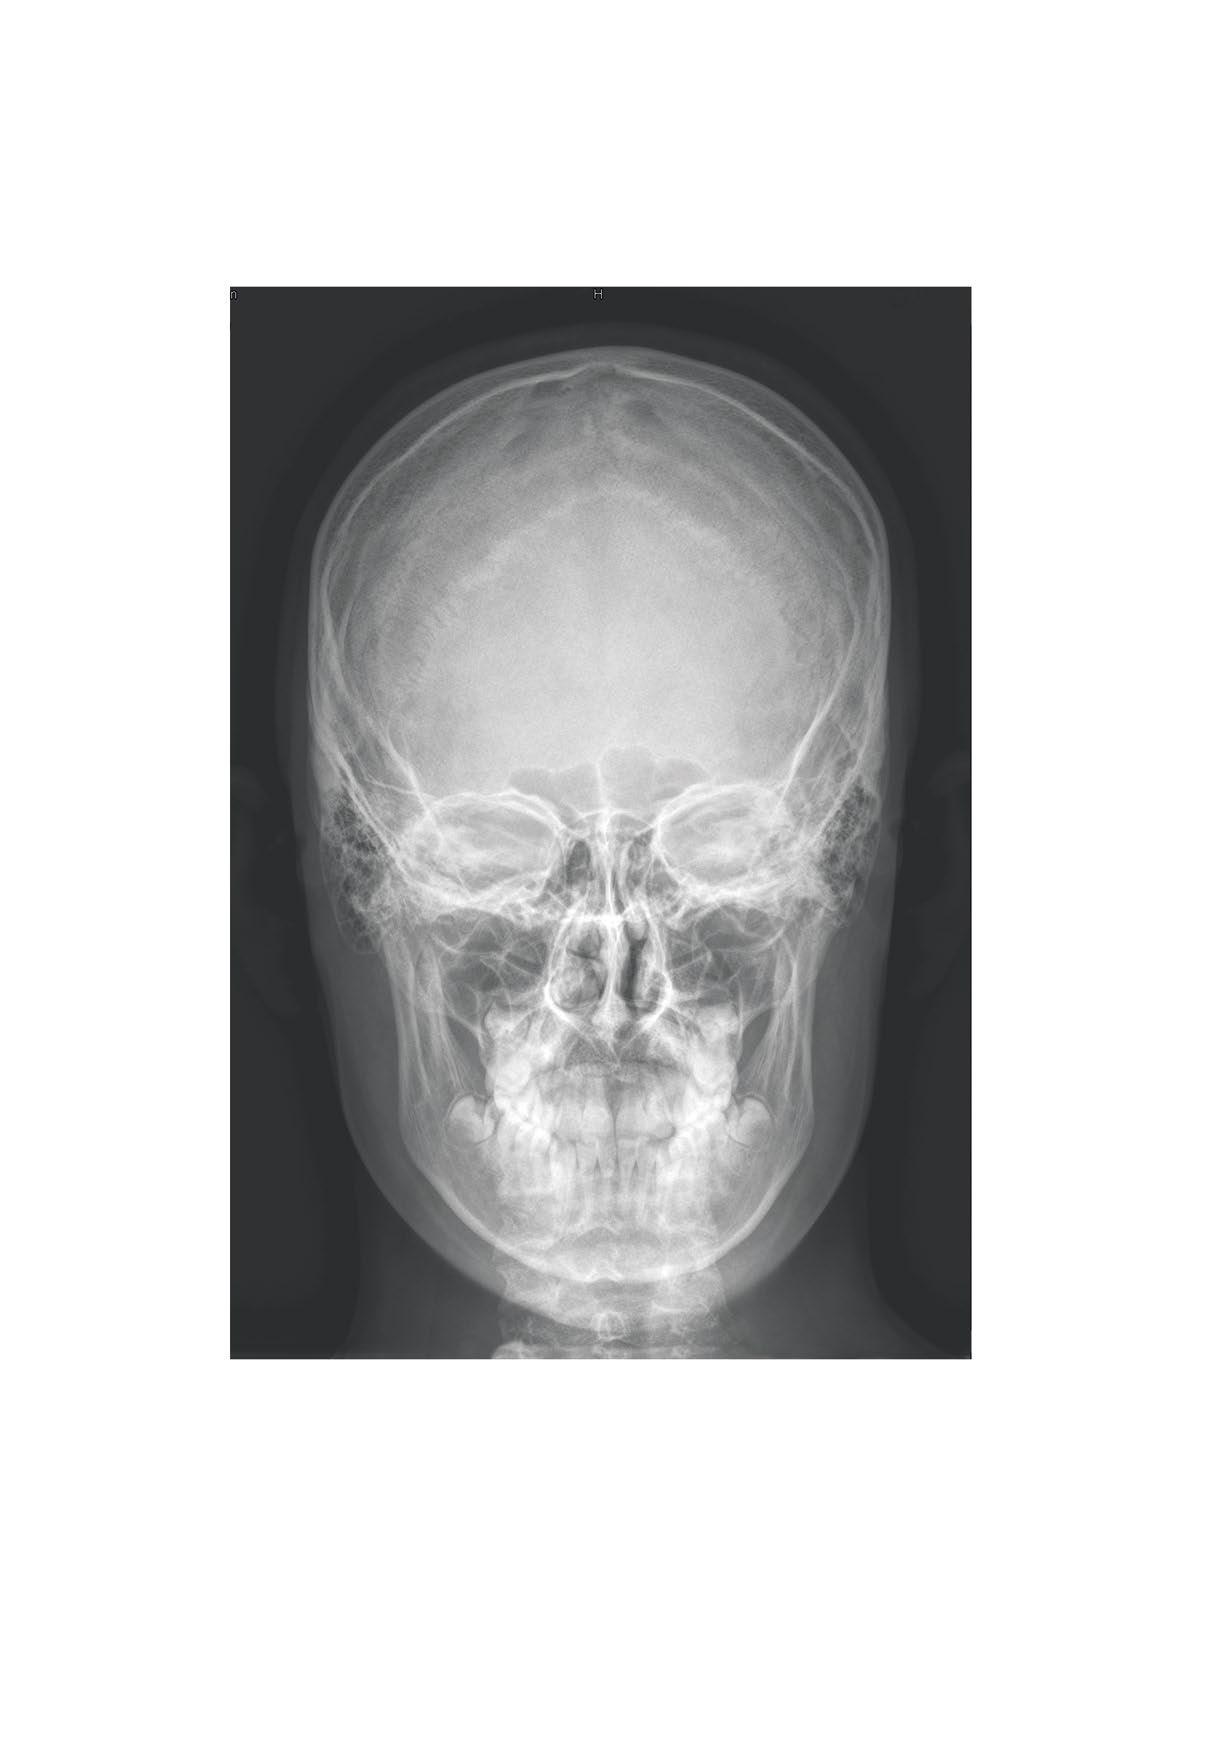

Skull, X-ray, posterioanterior view, boy, 15 years Hlava

Cranium, RTG lebky, zadopřední projekce, chlapec, 15 let

sutura coronalis

os frontale

arcus superciliaris

os nasale

canalis opticus

ala major

foramen zygomaticofaciale

foramen infraorbitale

apertura piriformis

spina nasalis anterior

glabella os zygomaticum

foramen frontale

ala major ossis sphenoidalis

fissura orbitalis inferior arcus zygomaticus os temporale

fissura orbitalis superior

maxilla

mandibula

foramen mentale

sutura sagittalis

concha nasalis media

concha nasalis inferior angulus mandibulae